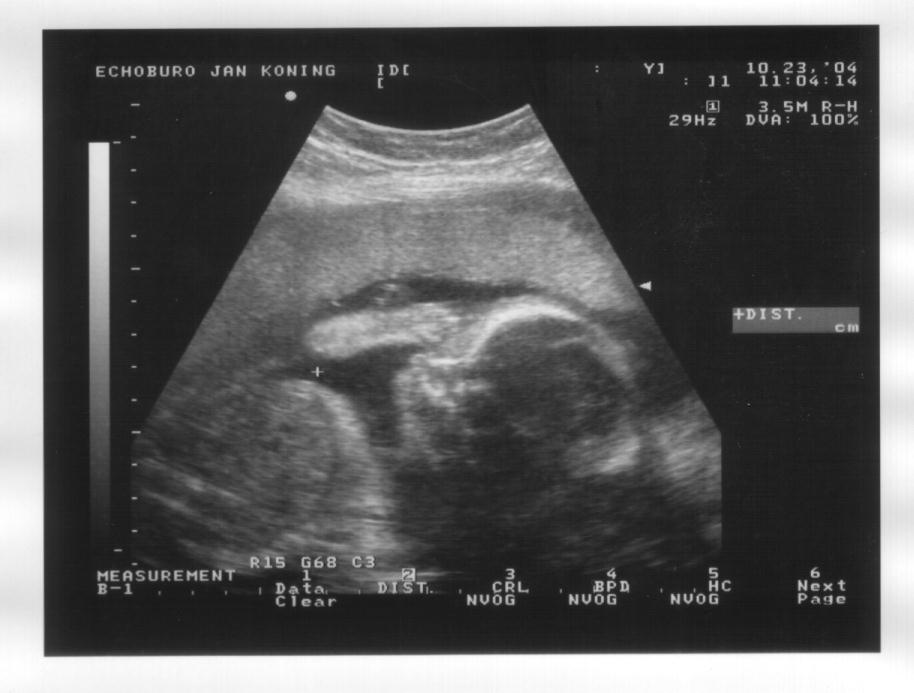

23 oktober 2004

Rechts: Vooraanzicht, gezicht met duidelijk de ogen, neus en mond, en 2 vuistjes